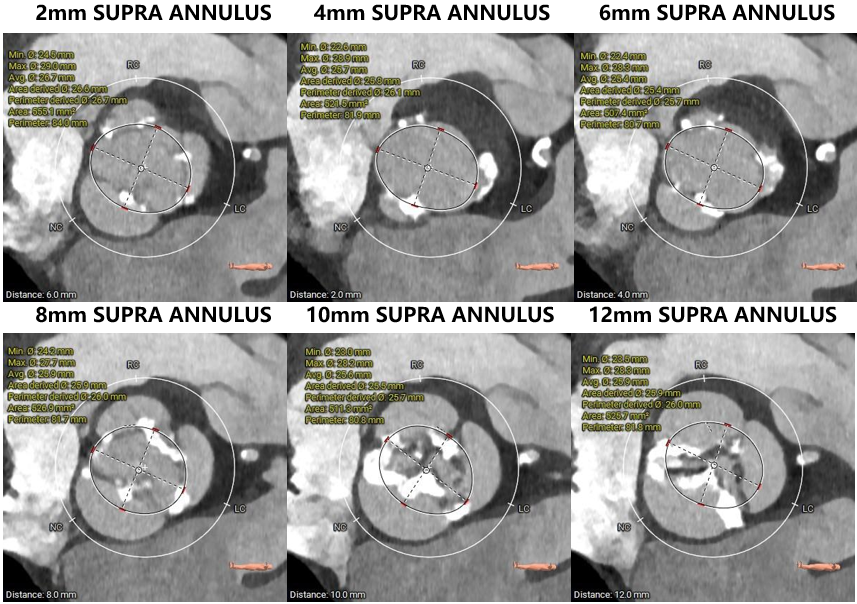

瓣环上解剖结构评估

主动脉根部评估

1.主动脉瓣瓣环周长90.6mm,平均周长径28.8mm。

2.主动脉瓣成三叶式,瓣叶明显增厚伴重度钙化,钙化均匀分布与三窦瓣叶上。

3.左右冠脉开口高度可。

4. 左室腔内径较大,心室壁厚度可,横位心,升主动脉扩张。

1. 考虑到患者瓣叶有增厚伴重度钙化,结合瓣环大小,downsize选择预装AV29瓣膜。

2. 考虑到患者升主动脉扩张,夹层、血管破裂等并发症风险提升,所以术中可能需要圈套器辅助过弓。

3. 根据术前CT评估,跨瓣角度为RAO 10° CAU 14°(右窦中心)左右,球囊预扩角度为为 RAO 6° CAU 6°(左冠切线位)左右,释放角度为释放角度 角度 RAO 25° CAU 35°(左右重合位)左右。使用23mm球囊预扩,充分利用沛嘉TaurusElite产品可回收的功能,瓣环上0mm高度释放,为高概率发生的瓣膜下滑留下缓冲位置。